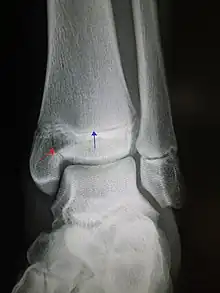

Fracturas del tobillo

Consiste en la rotura de alguno de los huesos que componen la articulación.